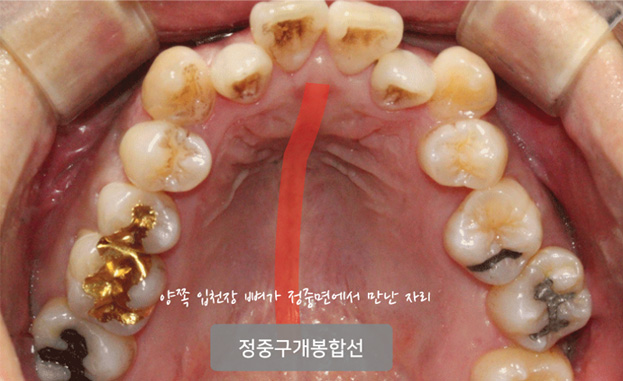

악궁확장은 RPE나 MARPE라는 장치를 통해서 정중구개봉합을 열어주는 방법을 사용합니다.

환자분들께는 이해가 쉽도록 "성장판을 열어준다"라고 표현을 하기도 합니다.